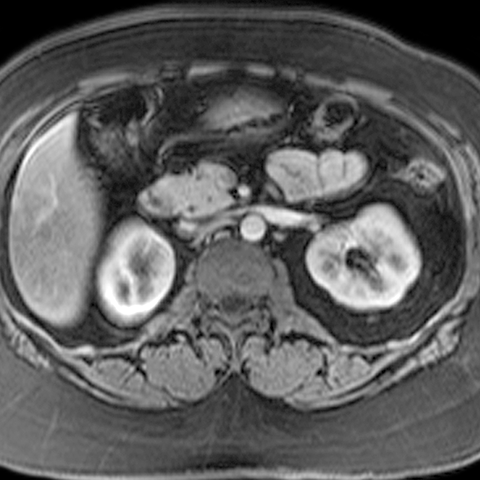

Normal Pancreas, Axial MRI [3 of 3]